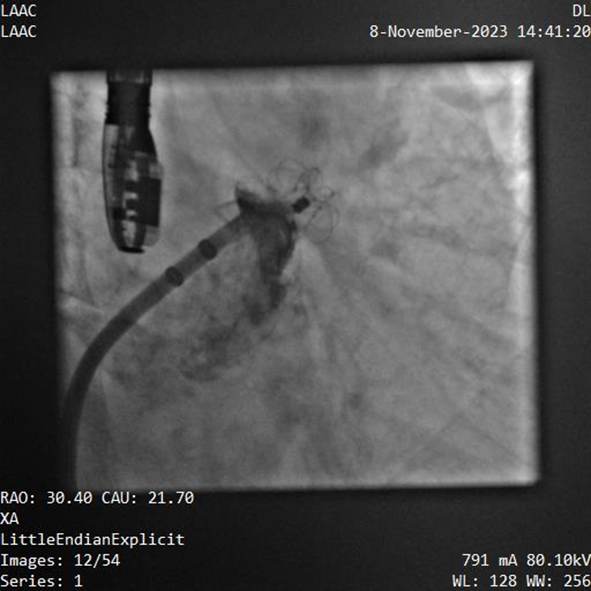

器械釋放后造影示封堵器展開良好,封堵完全